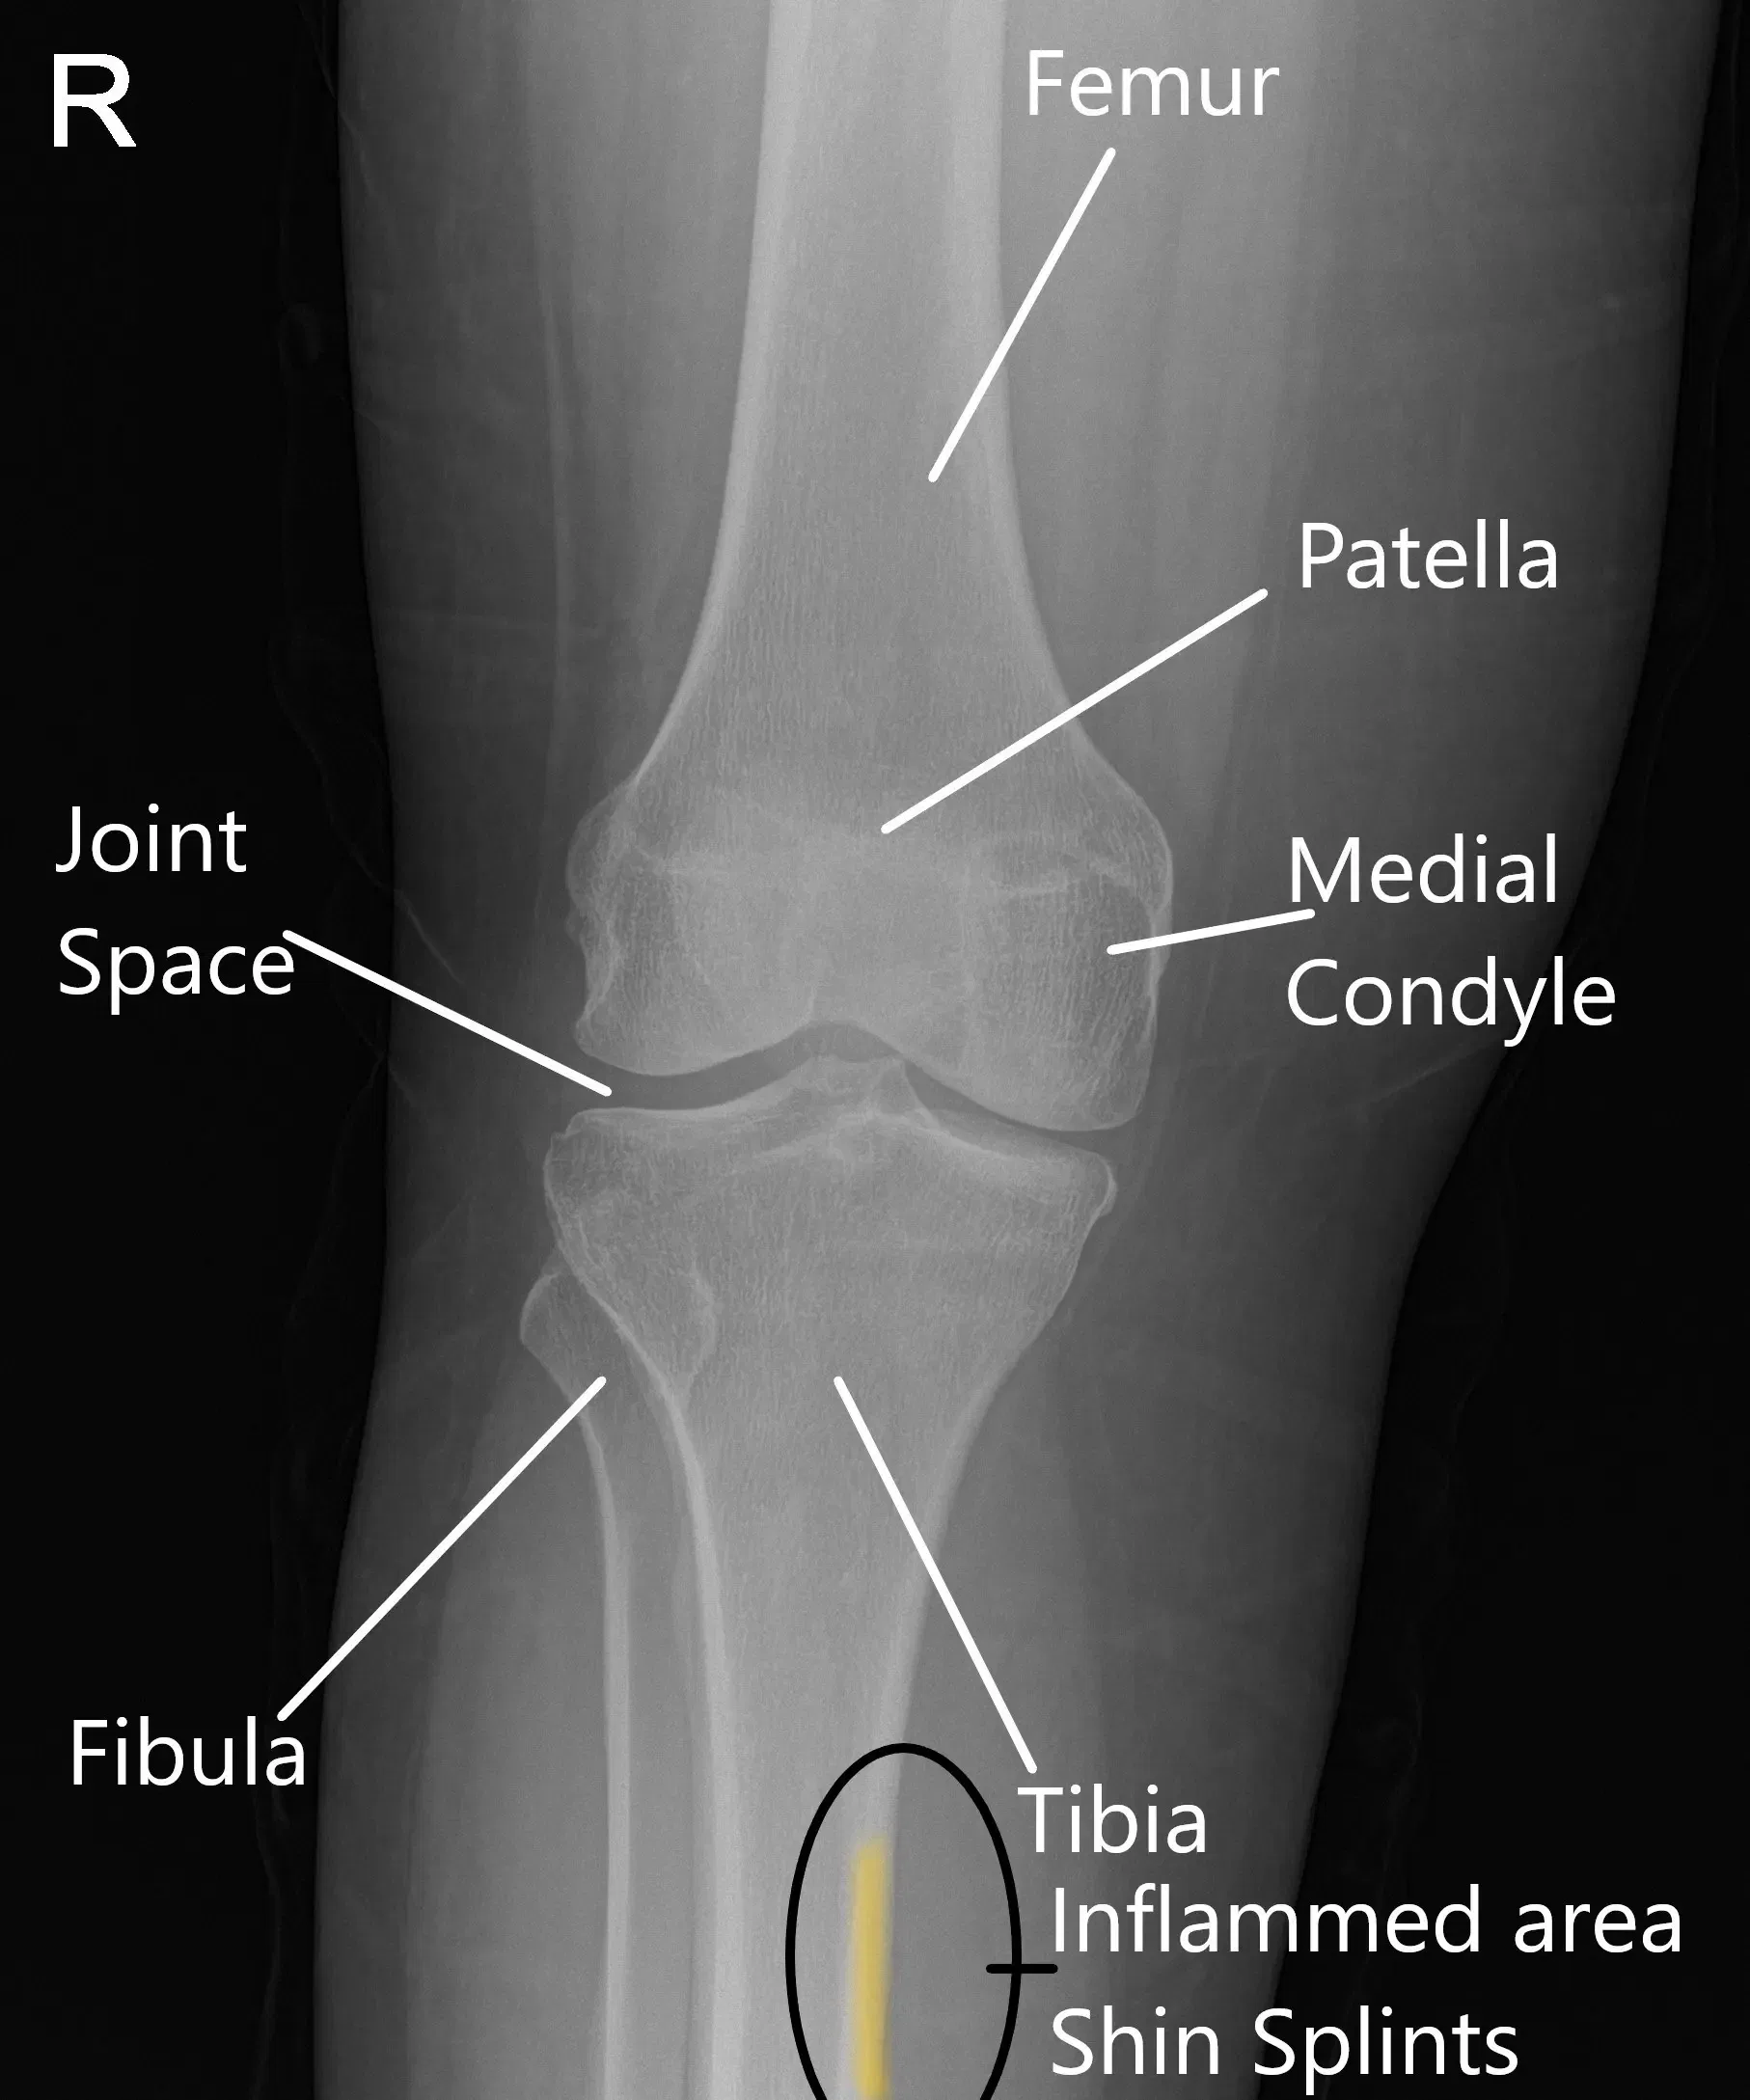

X-ray of a normal knee showing the area of inflammation in shin splints.

The tibia, or shinbone, is the long bone in the lower leg. It is surrounded by muscles, tendons, and the periosteum. The periosteum helps to protect and nourish the bone, while muscles like the calf muscles and the tibialis anterior are responsible for movement. During activities like running or jumping, these muscles contract and apply force to the shinbone. If the muscles and tendons are overstressed, it can lead to inflammation and pain along the inner edge of the tibia.

The diagnosis of shin splints begins with a detailed history of physical activity, including any changes in training intensity or volume. A physical examination focuses on tenderness along the inner part of the shinbone, and the doctor may assess the alignment of the feet and legs to identify any contributing factors. X-rays are often used to rule out stress fractures, while MRI or bone scans may be requested if the physician suspects a more serious underlying condition.